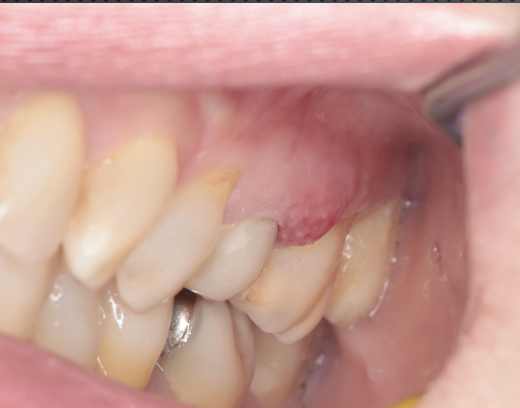

初診時

左上の治療中の歯肉が腫れて痛い。根管治療を何度も繰り返しているが一向に良くならない。

抜歯時の状態

抜歯してみると、歯根破折がみられ、その周囲には比較的大きな膿疱ができていました。これではいくら治療しても治りません。